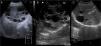

Se trata de un quiste verdadero (posee un recubrimiento epitelial) que surge como una anomalía en el desarrollo de la vía biliar intrahepática. Ecográficamente se define como una lesión anecoica, sin ecos internos, bien delimitada por una pared fina y con refuerzo acústico posterior (quiste simple) (fig. 1C). En ocasiones puede contener ecos internos, septos de diferente grosor, adelgazamiento o irregularidad parietal, e incluso puede parecer sólido, obligándonos a establecer un diagnóstico diferencial entre la posible complicación de un quiste simple por infección o hemorragia o la existencia de un quiste complejo de otra naturaleza.

Enfermedad poliquística hepatorrenal2Con diferente implicación pronóstica según se trate de la enfermedad autosómica recesiva infantil o enfermedad autosómica dominante del adulto. En el estudio ecográfico hallamos la presencia de múltiples quistes simples con la semiología antes descrita, a nivel renal y hepático (con discreta predilección por el lóbulo hepático izquierdo) (fig. 1B).

Quiste multivesicular. Imagen patognomónica, caracterizada por la presencia interna de múltiples cavidades que constituyen las vesículas hijas (cada uno de ellos delimitados por una pared gruesa y con material ecogénico en su interior) (fig. 1A).